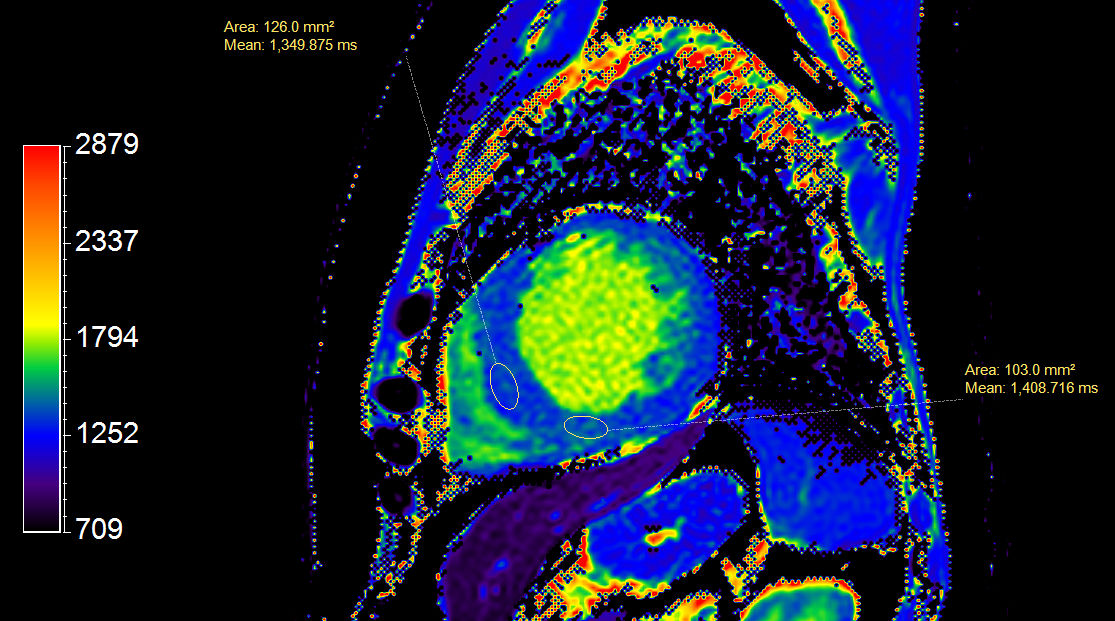

Short axis view T2 Map